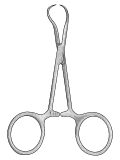

| Mosquito forceps |

|

Hemostatic forceps | |